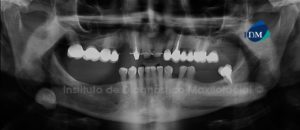

Paciente femenino, 55 años de edad acude al Instituto de Diagnóstico Maxilofacial (IDM) para su evaluación previo a tratamiento integral y colocación de implantes. A